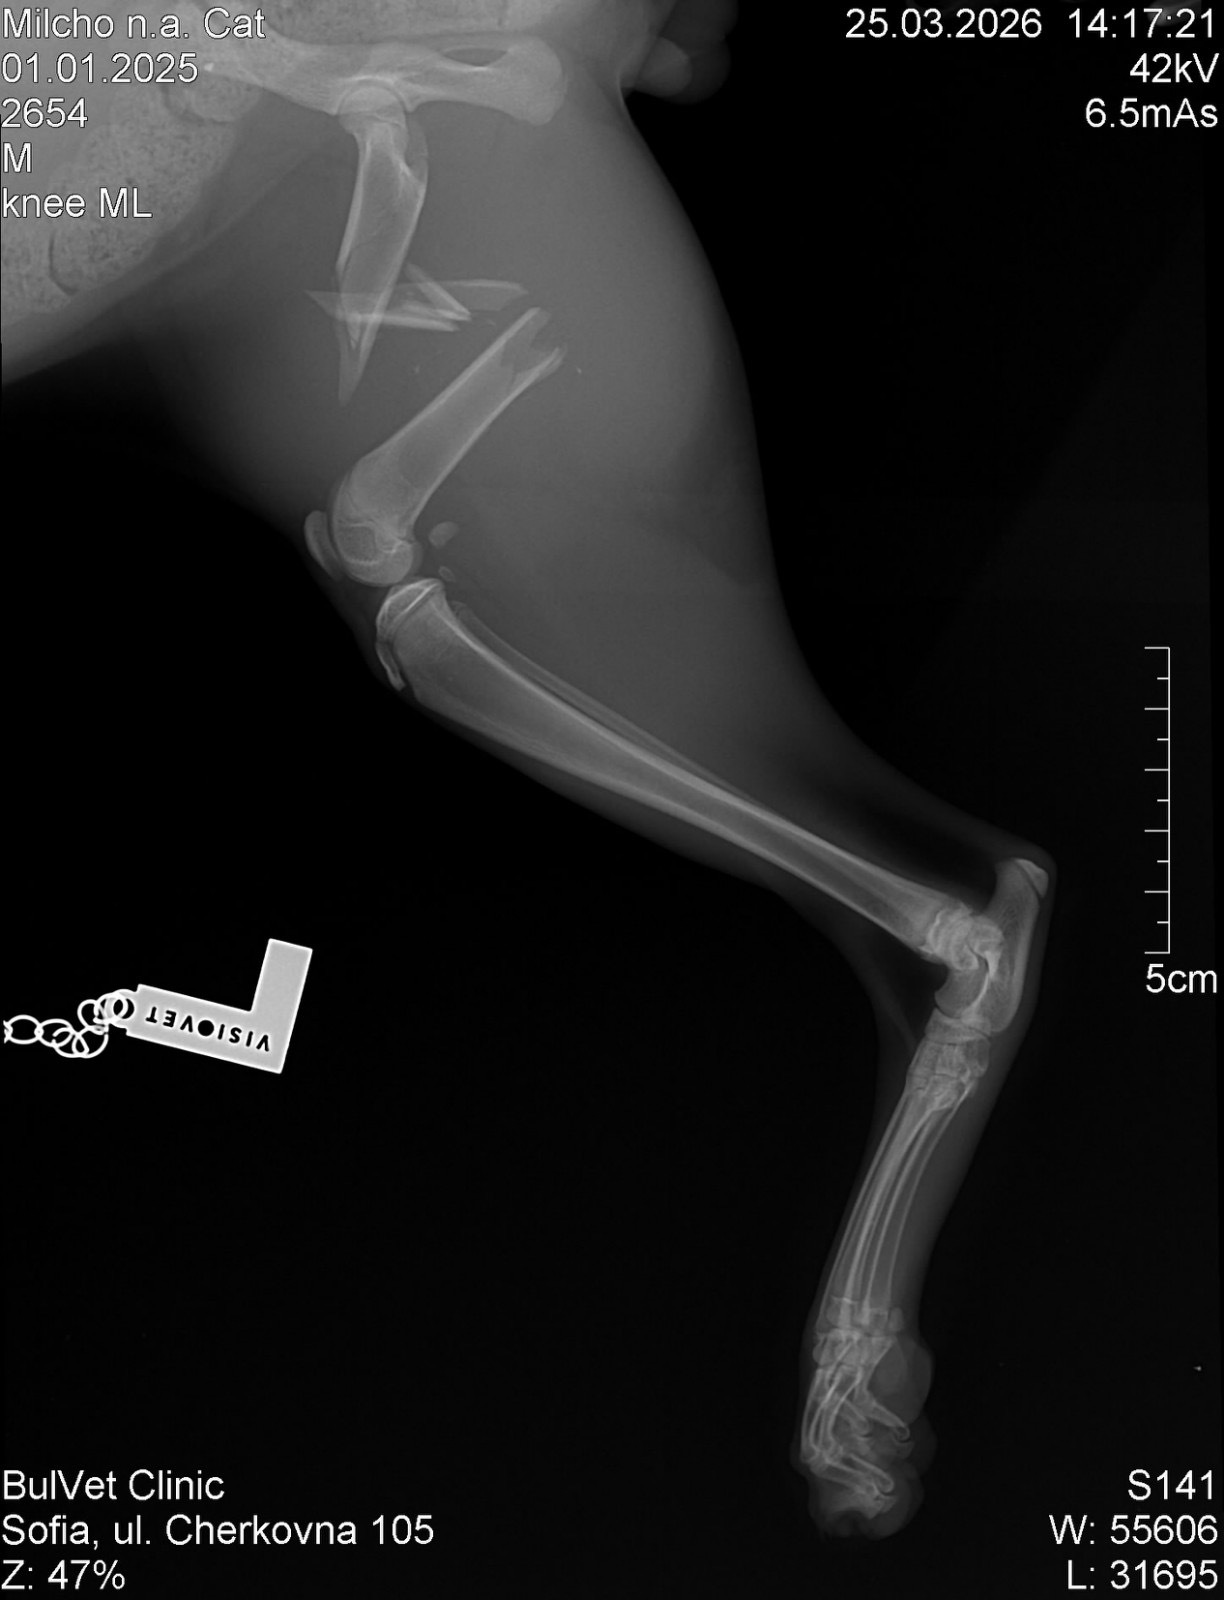

Искаме да ви запознаем с едно малко геройче – котето Милчо, което цяла седмица се въртеше из групите с надеждата някой да му помогне…Милчо е от Петрич, но там не се намери възможност да бъде опериран. Успяхме да го транспортираме до София, където днес му беше направен специализиран ортопедичен преглед… и новините не са добри.

Милчо е със:

– сериозна фрактура на крачето( снимки от рентген - в коментарите)

– множество счупвания

– травми в областта на таза

– силно изтощен и дехидратиран

Очевидно са минали дни след удара, който е преживял…

Съединителната тъкан вече започва да се разраства, което означава само едно — НЯМАМЕ ВРЕМЕ.Операцията трябва да се направи СПЕШНО, ако искаме Милчо да има шанс да ходи отново на четири лапички…